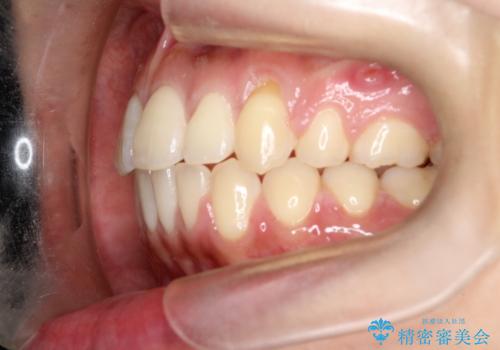

- 前歯の凸凹を主訴に来院されました。

予想治療期間2年でしたが、実際は1年半ほどで終了し満足していただきました。

小臼歯抜歯(上顎4番)して矯正治療を行なったことで、口元もスッキリしました。